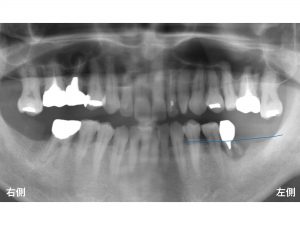

以下が初診時です。

下顎左側奥歯は、すでに欠損している方で、

現在一番奥歯になる歯がグラグラしている状態でした。

診査の結果、下顎左側の奥歯は、

根が折れている状態でした。

歯根破折です。

感染による骨吸収をみてきましょう。

まず、骨吸収が起こる前の骨の位置が以下の青線です。

そして骨吸収した現在の状態を赤線で書いてみます。

青線から赤線まで骨が吸収してしまったのです。